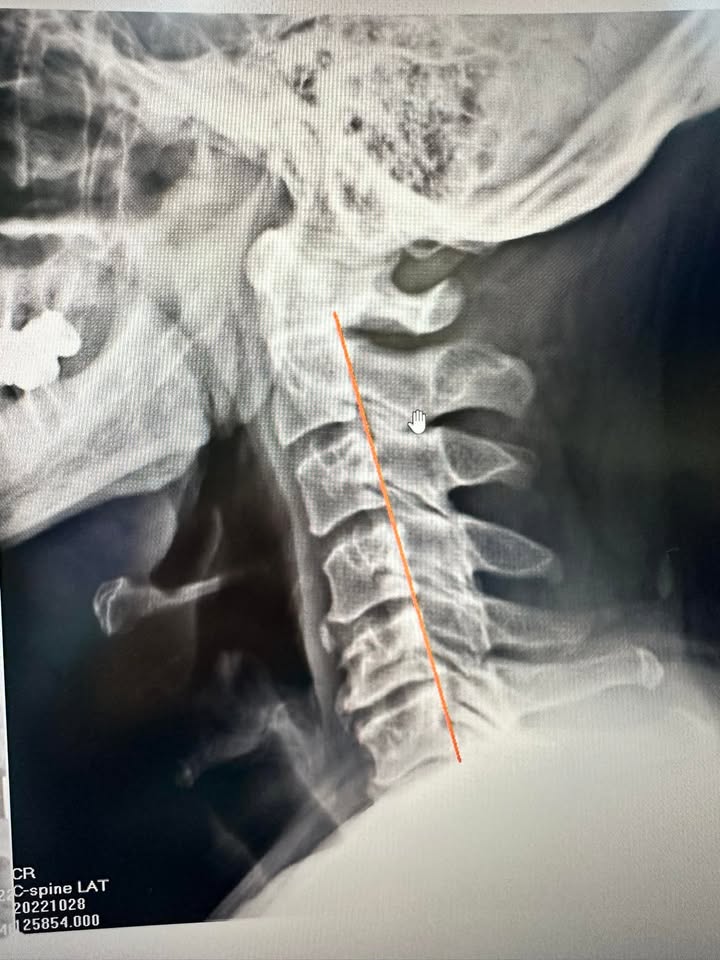

故事的開始,並不美好。50歲的張先生,是新北市汐止的一名普通上班族。長年的電腦工作和不良姿勢,像一個隱形的枷鎖,逐漸讓他的頸椎從原本健康的C字形,變成了一條毫無生命力的直線。肩頸僵硬、頭暈、耳鳴,甚至胃脹氣、胸悶,這些像是不速之客的症狀,無情地打亂了他的生活。更讓他痛苦的是,那種不被理解的孤獨感,甚至讓他覺得自己成了一個「無藥可救」的人。

▶️ 「交感神經型頸椎病」是一種由頸椎退化、變形或壓迫交感神經引起的綜合症狀。頸椎內的交感神經控制多種重要功能,當受到壓迫或刺激時,可能導致頭暈、耳鳴、胸悶、心悸、視力模糊、胃脹氣等不適症狀。這種病症通常與長期的不良姿勢、頸椎受傷或退化有關。診斷通常需藉助核磁共振等影像學檢查,確定病變位置與嚴重程度。治療以非手術為主,包括頸椎減壓、針刀療法及最後考慮神外手術調整,幫助釋放神經壓迫並改善症狀。針對早期病變,及時治療可以顯著提升生活質量,減少進一步惡化的風險。